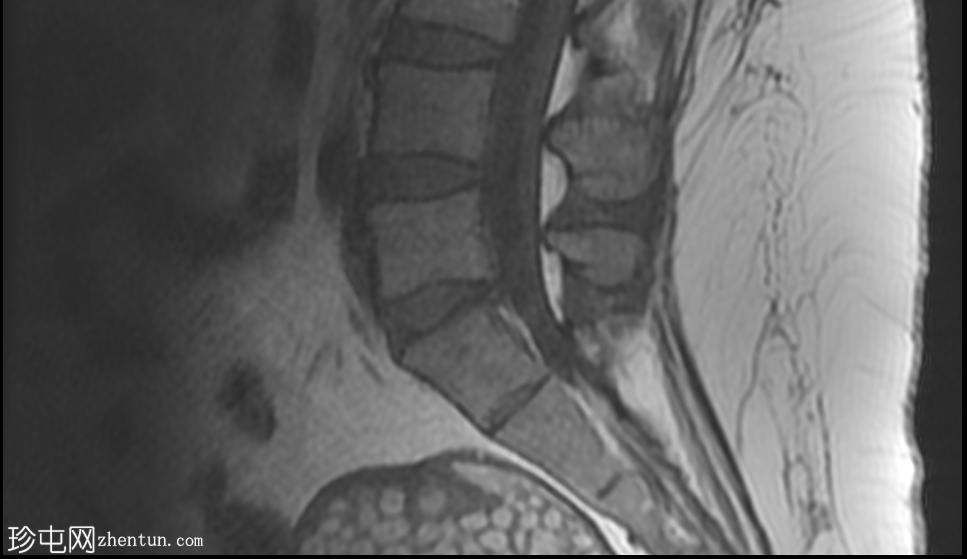

矢状位

T2加权像

4.png

盆腔可见部分囊性肿块,内含脂肪球。